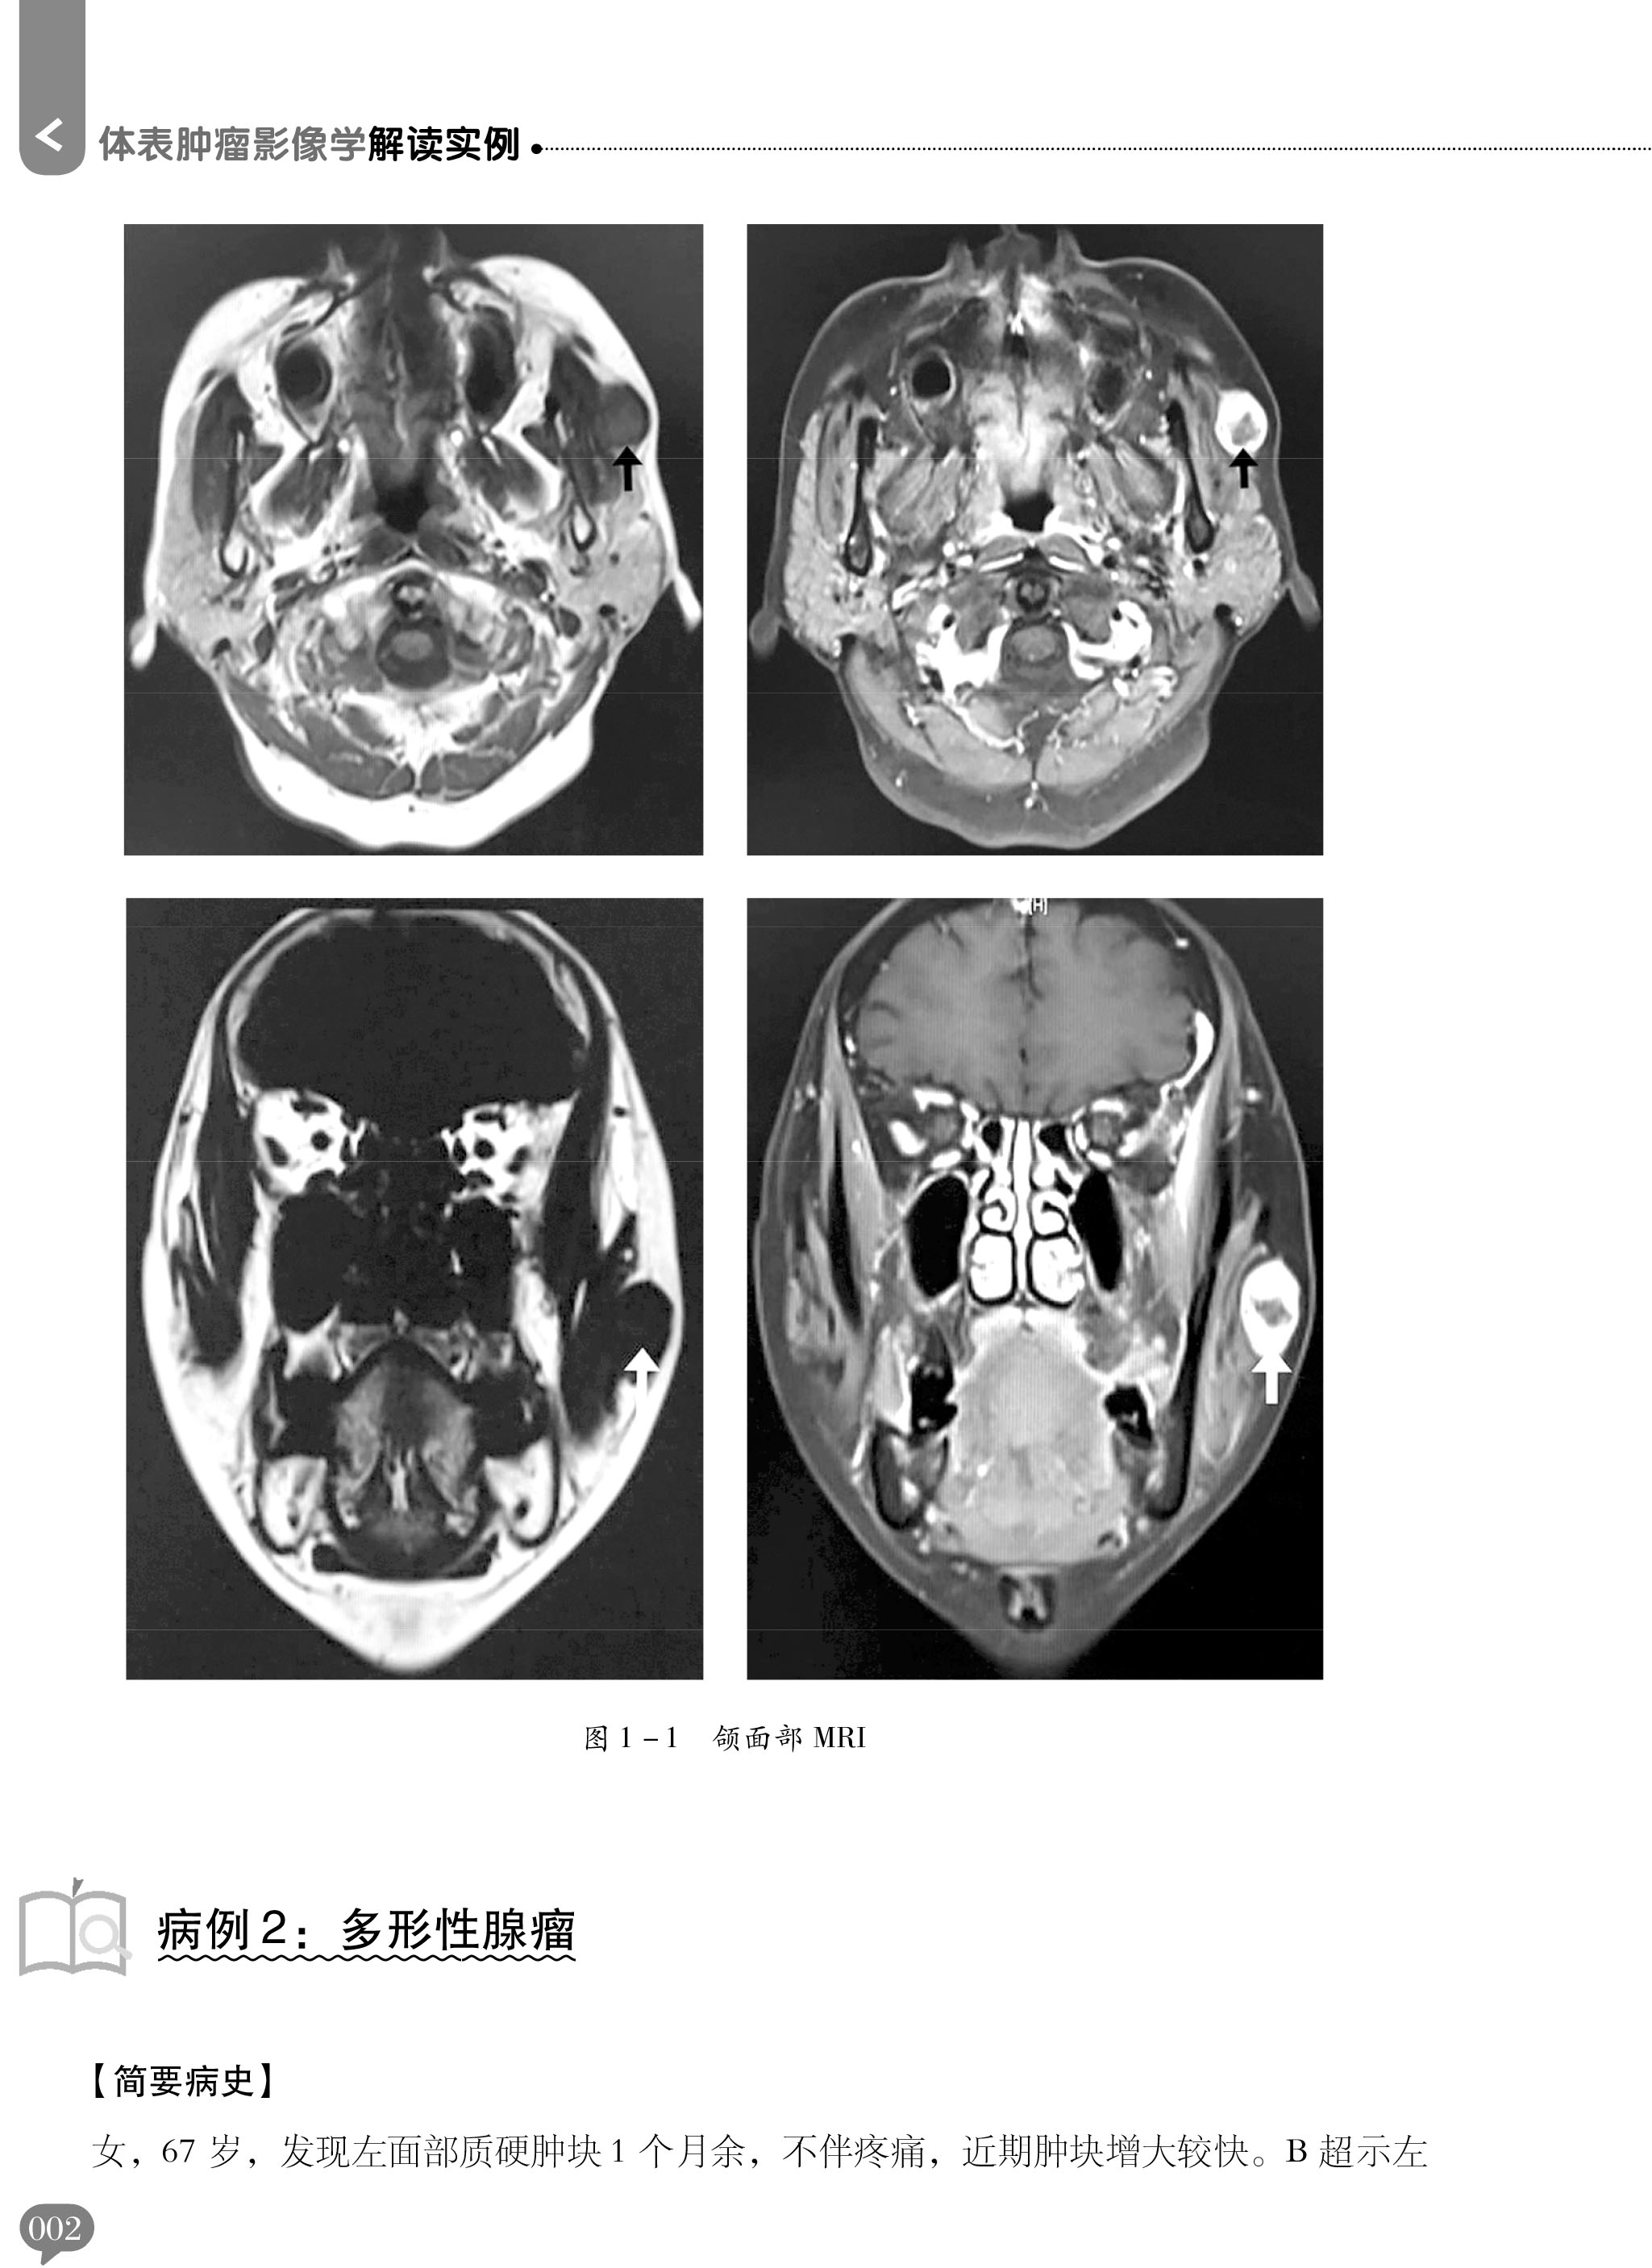

朱吉 学习参考书 主编 辽宁科学技术出版 9787559116024 体表肿瘤影像学解读实例 社 可为影像科医师提供参考及相关专业学生